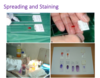

pictures showing spreading and staining

a blob of material si spread onto two slides, one into alcohol and one to dry and then stained

staining overall takes baout 5 minutes